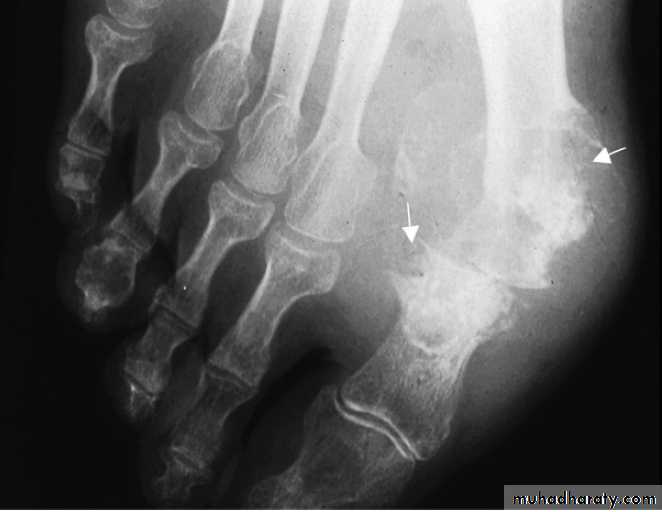

Plain radiographyShow changes of many bone and joint diseases . Radiographs are of diagnostic value in osteoarthritis

cysts and calcified loose bodies within the synovium . Radiographs may show erosions and sclerosis of the sacroiliac joints and syndesmophytes in the spine in seronegative spondyloarthritis. In peripheral joints, so-called proliferative erosions, associated with new bone formation and a periosteal reaction, may be observed.

In tophaceous gout, well-defined punched-out erosions may occur .